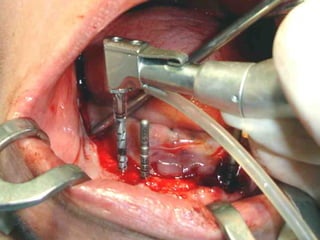

Segundo tiempo quirúrgico para aplicar la estructura.

Estructura en íntimo contacto con la superficie ósea, quedando los postes

fuera de la fibromucosa gingival..

Sutura de colgajos que cubren la estructura, dejando los postes bien visibles.

Segundo tiempo quirúrgicopara aplicar la estructura.

Estructura en íntimocontacto con la superficie ósea, quedando los postes fuera de la fibromucosa gingival..

Sutura de colgajosque cubren la estructura, dejando los postes bien visibles.